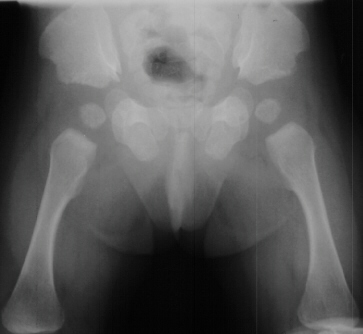

RADIOGRAPHS:

Plain x-ray's showed a sixth metacarpal and phalanx on the ulnar border

of both hands

.

The distal phalanges are shortened relative to the proximal and distal

segments. The pelvis

has

small, squared iliac crests with spikes of bone at the triradiate cartilages.

The tibial segments

are

disproportionately shorter than the femoral segments.

- Characteristic features of the pelvis includes:

- small iliac crests and sciatic notches

- originating from the triradiate cartilage a distally directed spike

of bone